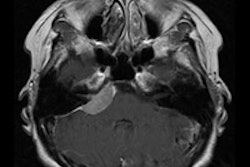

Images were examined in the axial plane by three experienced readers, who scored them visually for coronary and aortic calcifications. Each of the four main coronary arteries were scored separately (scale 0-3), then added into a single score for the coronary artery tree (0-12). The aorta was scored as to calcification in the ascending (0-3), descending (0-3), and supra-aortic arteries branching from the aortic arch (0-2) and added into a single score for the thoracic aorta (0-12).